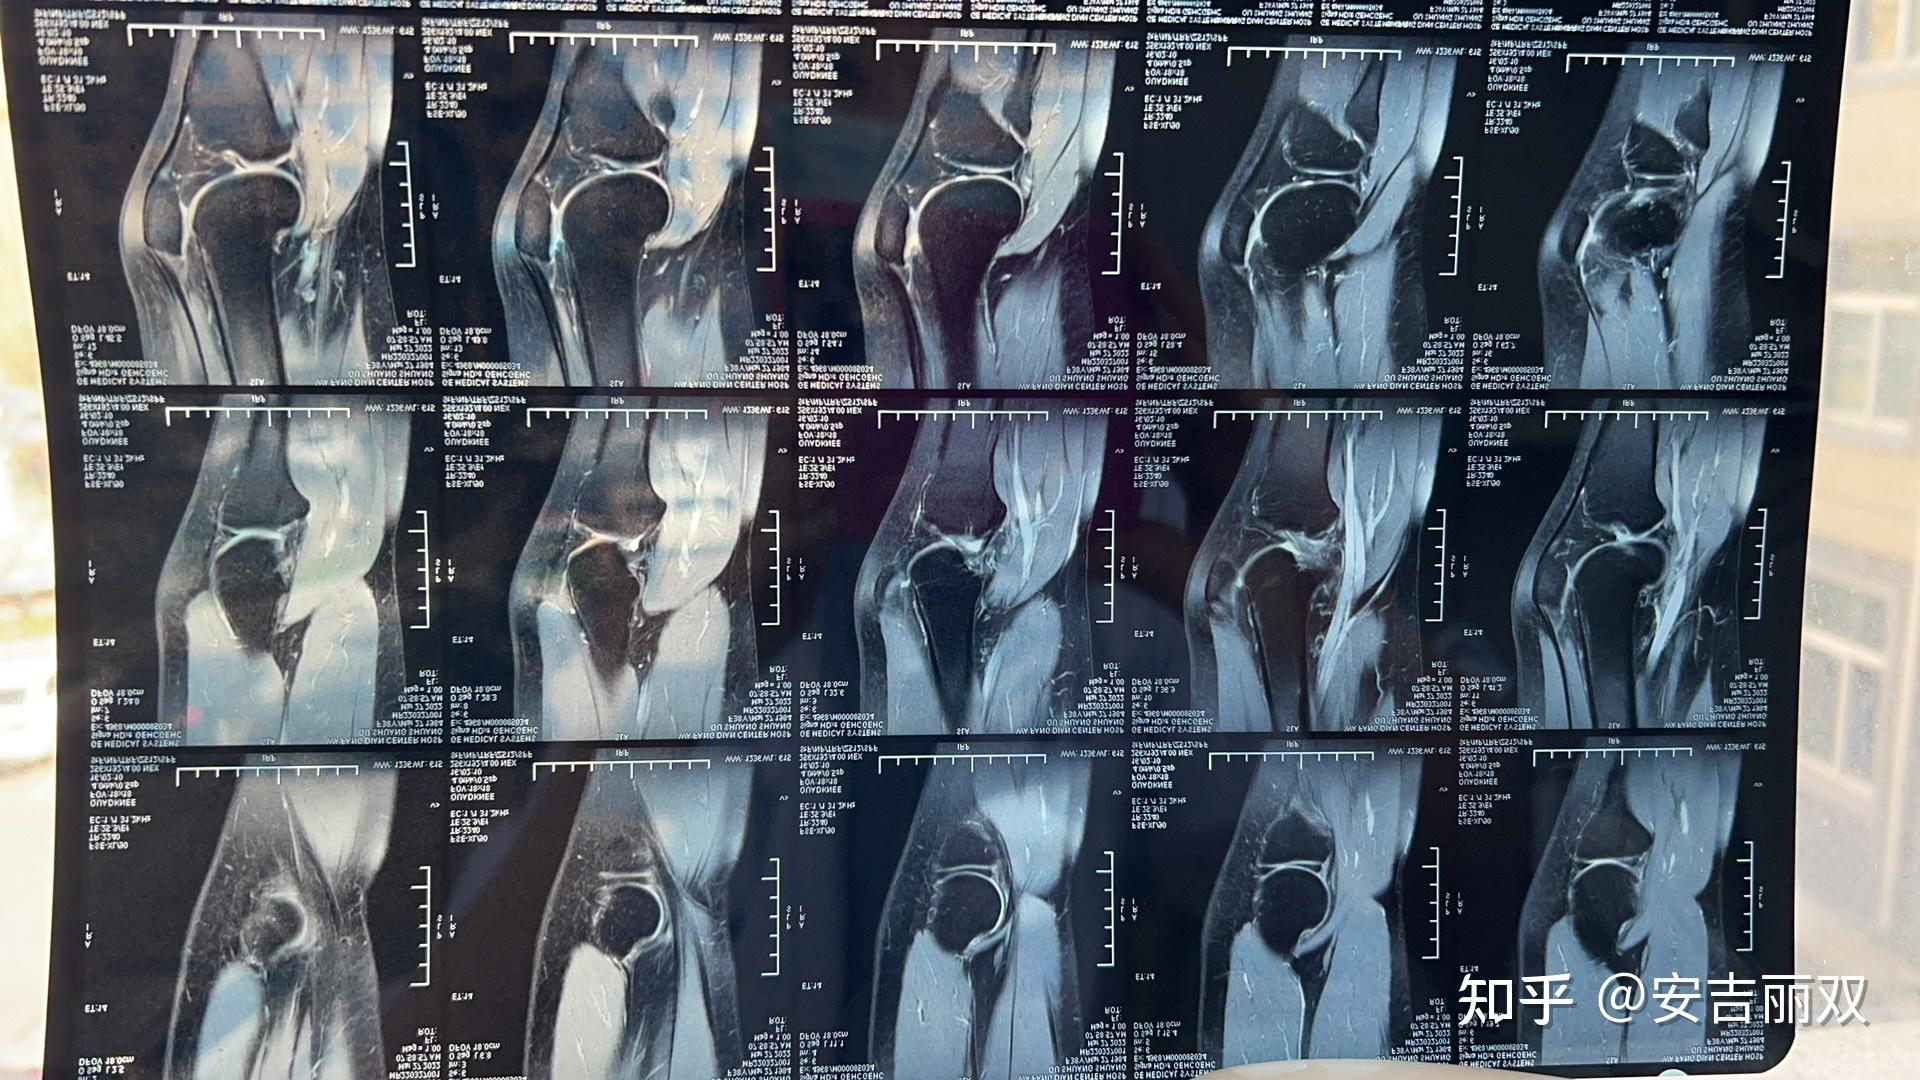

半月板损伤保守治疗纪录 - 知乎

图片尺寸1920x1080